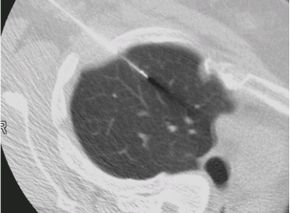

当院における早期肺がんに対する診療と治療の流れ

胸腔鏡手術の実際

胸腔鏡Hybrid VATS(ハイブリッドバッツ:体に小さく開けた創から病変を直接観察し

ながら手術を行う)では、皮膚切開は2箇所(1cmの胸腔鏡挿入口と4〜6cmの手術操作

口)で手術を行います。

(手術の前には病変の場所にCTガイド下にてマーキングを行います。)